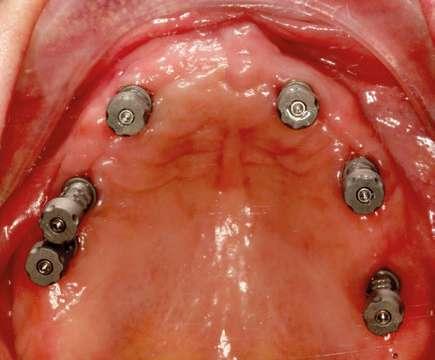

Acto quirúrgico

En primer lugar, se llevó a cabo una primera fase higiénica y desinflamatoria mediante profilaxis y RAR inferior.

A la hora de la cirugía, una vez verificada que la plantilla está en la posición correcta, fresamos a través del tubo del tornillo de anclaje mediante la fresa espiral guiada de 1,5 mm x 20 mm hasta el tope de la fresa e introducimos los tornillos de anclaje guiados completamente dentro del tubo. En este caso, hicimos un abordaje con colgajo, realizamos el fresado piloto guiado utilizando las fresas guiadas seleccionadas según el informe del plan de tratamiento, seguidamente retiramos la plantilla quirúrgica y continuamos con la preparación de los lechos y la colocación de los implantes. Se utilizó la secuencia recomendada por el fabricante en hueso tipo III para colocar los implantes. Los torques de inserción finales fueron entre 32 y 50 Nw.

Los implantes fueron colocados en una posición subcrestal. Siguiendo las recomendaciones de Tomas Linkevičius, si los tejidos son finos, simplemente enterrando los implantes a una mayor profundidad en el hueso va a servir para compensar la falta de espesor de tejido blando. Al enterrar 1,5 mm los implantes por debajo de la cresta ósea y si tenemos un espesor vertical de tejido blando de 2 mm, habrá en total 3,5 mm de espacio biológico. Esto es suficiente para la formación de un sello periimplantario con lo que se evita la reabsorción ósea. (Fig. 9, 10 y 11)

caso clínico

Se monitorizó la evolución de la cicatrización durante las semanas siguientes y se fue adaptando la prótesis provisional a los cambios gingivales mediante silicona de rebase blando. (Ufi Gel SC Voco). Pasados cuatro meses, procedimos a realizar la exposición de los implantes y la conexión de los pilares Multi-unit Xeal™ rotatorios mediante un protocolo One abutment- One time. Durante la segunda cirugía, nos aseguramos de dejar un tejido blando de suficiente grosor y altura de encía queratinizada que nos garantice un mantenimiento del hueso crestal. Se seleccionaron las alturas y angulaciones de estos y se colocaron a 35 Nw de torque. La topografía y las propiedades químicas de estos pilares han sido diseñadas para facilitar la adhesión del tejido blando al pilar y así tener una mejor barrera que proteja el hueso subyacente. Al colocar estos pilares logramos igualar las alturas de las plataformas de los implantes, siendo más cómoda la realización de la prótesis definitiva y también mejorando la higienización de la futura prótesis. (Fig. 12 y 13).